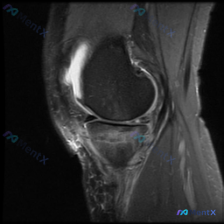

本来找半月板异常,结果MRI核心问题在这?膝关节影像分析分享

刚看到这个膝关节MRI读片的病例,有点典型,整理出来和大家分享一下思路。

这是一份膝关节矢状位MRI影像,序列为T2WI或PDWI-FS,对软组织、水肿、韧带病变显示清晰。

影像学核心发现

- 骨骼与关节软骨:髌骨后方关节软骨面不平整,髌骨软骨下骨可见片状高信号影,提示骨髓水肿或软骨下骨损伤;股骨滑车也可见骨髓信号改变,其余骨皮质轮廓基本正常

- 韧带肌腱:髌韧带走行连续,但髌骨下髌下脂肪垫附近软组织信号杂乱;股四头肌腱连续性尚可

- 关节腔与软组织:髌上囊及髌前区域可见明显液体高信号,提示关节积液;髌骨前方软组织、髌下脂肪垫信号混杂高信号,提示炎症水肿改变

- 本次影像层面未见明显骨折、关节脱位、占位性病变

这份影像所有明确的阳性发现都集中在髌股关节区域,而且完全可以用「髌股关节功能障碍继发局部炎症」来一元化解释所有表现,比单独下多个诊断更合理。

目前结合影像信息,最符合的结论是:髌股关节疼痛综合征/髌骨软化症,合并髌前滑囊炎、Hoffa脂肪垫炎,半月板异常无明确证据,可能性较低。